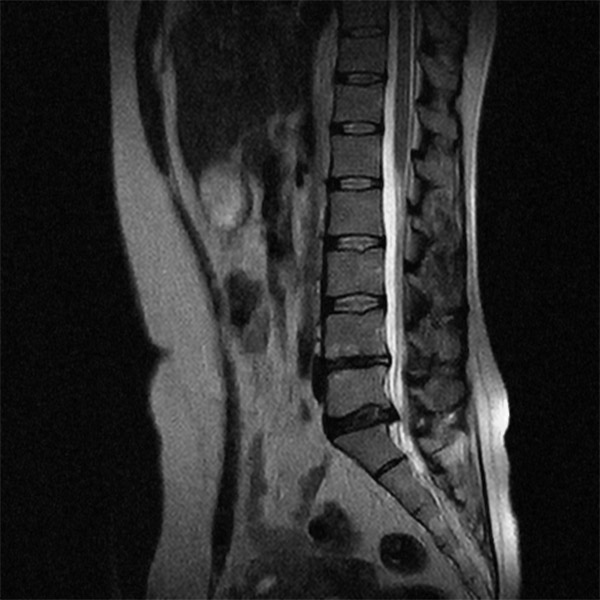

Мрт картина дегенеративно дистрофических изменений пояснично крестцового отдела позвоночника